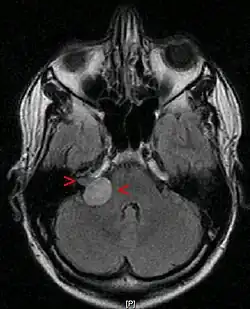

Ein Akustikusneurinom (kurz AKN oder AN) ist ein gutartiger Tumor, der von den Schwann’schen Zellen des vestibulären Anteils des VIII. Hirnnerven, des Hör- und Gleichgewichtsnerven (Nervus vestibulocochlearis), ausgeht und im inneren Gehörgang, bei größerer Ausdehnung auch im Kleinhirnbrückenwinkel gelegen ist. Das Akustikusneurinom ist histologisch eigentlich als Vestibularis-Schwannom zu bezeichnen. Die Bezeichnung Akustikusneurinom ist aber klinisch üblich.[1] Es ist der häufigste Kleinhirnbrückenwinkeltumor.

Diagnose des Akustikusneurinoms

Eine sichere Diagnose liefert nur die histologische Untersuchung nach einer Gewebeentnahme. Erstmals röntgenographisch dargestellt wurden Akustikusneurinome mit Erweiterungen des inneren Gehörgangs durch Salomon Eberhard Henschen (1910) und Hendrik Willem Stenvers (1917).[4] Klinisch relevante Tumoren können heute mit einer Magnetresonanztomographie (MRT) zuverlässig detektiert werden.

Bei Schwindel werden zunächst akute Infektionen ausgeschlossen, die ähnliche Krankheitsbilder ergeben. Eine auffällige Hörminderung wird durch ein Tonaudiogramm festgestellt. Danach wird eine Messung der frühen akustisch evozierten Potenziale (FAEP) durchgeführt, vor allem, wenn eine seitendifferente oder einseitige Schallempfindungsschwerhörigkeit vorliegt. Bei der Messung der FAEP zeigt sich ein Akustikusneurinom in der Laufzeiterhöhung der Signale vom Innenohr zum Stammhirn. Das liegt daran, dass durch das AKN die Myelinscheide der Nervenbahn beschädigt ist und die elektrischen Impulse nur noch unter Verlusten transportiert werden können. Bei deutlich seitendifferentem Kurvenbild bzw. seitendifferenten Laufzeitunterschieden der Potentiale sollte eine Magnetresonanztomographie des Schädels mit und ohne Kontrastmittel durchgeführt werden, um mit ausreichender Sicherheit ein Akustikusneurinom ausschließen zu können.